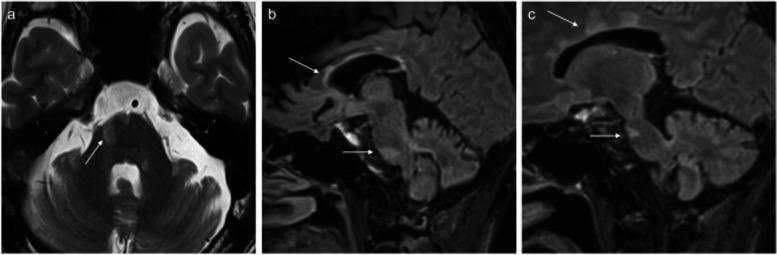

A 49-year-old male with multiple sclerosis exhibited persistent dull pain and paroxysmal electric shock-like pain in his bilateral maxillary molars and mandible. He was diagnosed with trigeminal neuralgia due to multiple sclerosis. Due to severe side effects, it was difficult to achieve adequate pain control with medication alone. By performing low-temperature radiofrequency thermocoagulation and pulsed radiofrequency of the Gasserian ganglion while monitoring masseter muscle contraction, a satisfactory and rapid analgesic effect was obtained without masticatory atonia.

一名49岁的多发性硬化男性患者双侧上颌磨牙和下颌出现持续性钝痛和阵发性电击样疼痛。他被诊断为继发于多发性硬化的三叉神经痛。由于严重的副作用,仅靠药物难以实现充分的疼痛控制。通过在监测咬肌收缩的同时对半月神经节进行低温射频热凝和脉冲射频治疗,获得了满意且快速的镇痛效果,且未出现咀嚼肌麻痹。